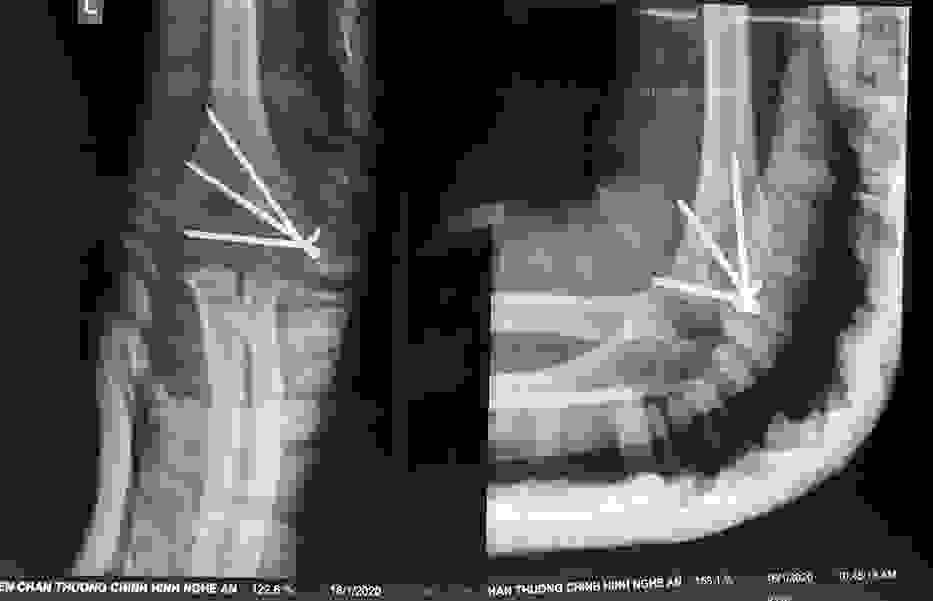

Phẫu thuật thành công ca bệnh hiếm gặp...khớp giả bẩm sinh xương chày

26/06/2019 17:00

Đã xem: 3534

Bệnh viện Chấn thương- Chỉnh hình Nghệ An, vừa phẫu thuật thành công cho bệnh nhi khớp giả bẩm sinh xương chày